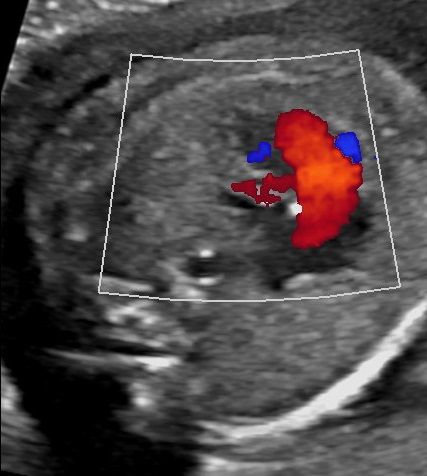

Online-Seminar "Fetale Echokardiographie"

Systematik der Untersuchung, Hinweiszeichen & Diagnose von Herzfehlern, Arrhythmien, I.Trimenon, Kasuistiken, ausreichend Zeit für Diskussionen, Fallbeispiele aus der Praxis, Quiz